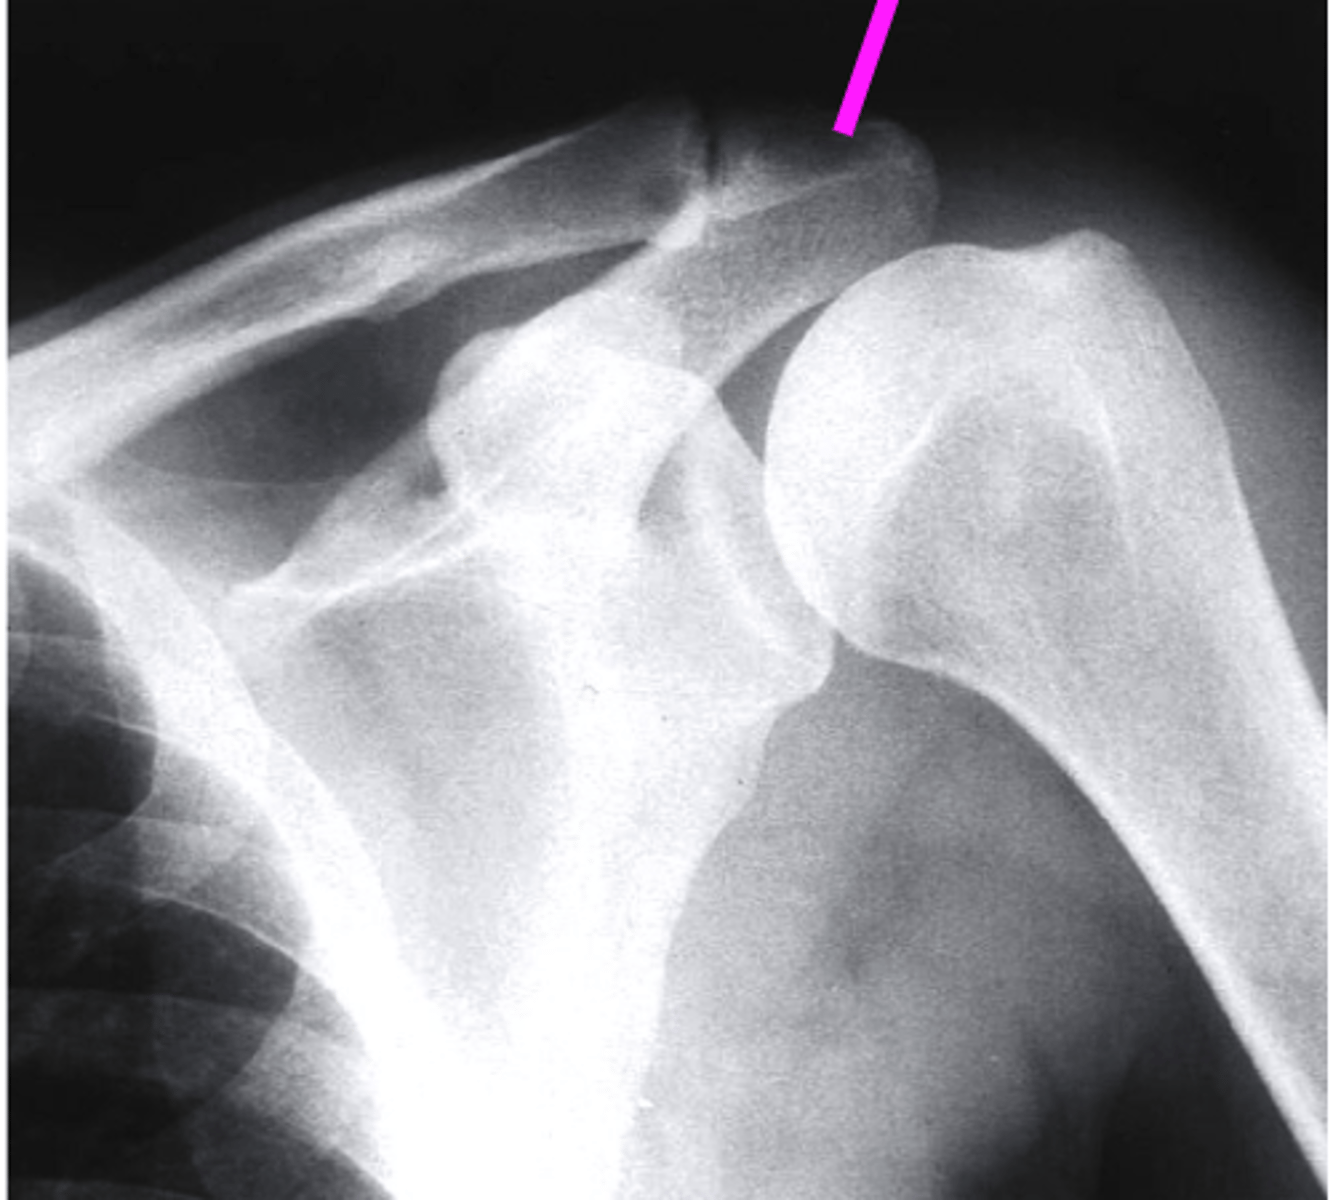

AP + IR

what view is this?

clavicle

what does the pink line point to?

spine of scapula

coracoid process

glenoid fossa of scapula

AC joint

acromion

Humeral Head

lesser tubercle